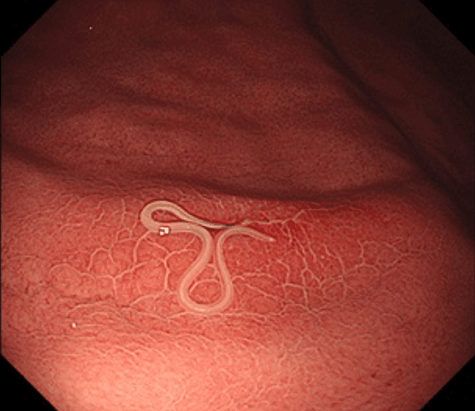

5.こちらは無症候例です。先程のものと比べると、周囲の浮腫が軽微です。